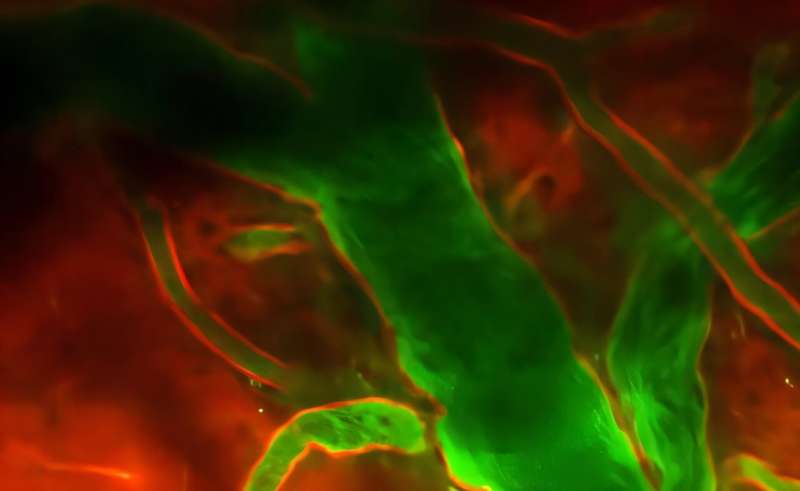

In addition to the immediate bleeding, traumatic brain injury (TBI) also causes dangerous brain swelling days later, as blood vessels begin to leak. Even if a person is rushed to the hospital, doctors have few options, aside from surgery, to stop the bleeding or the brain swelling.